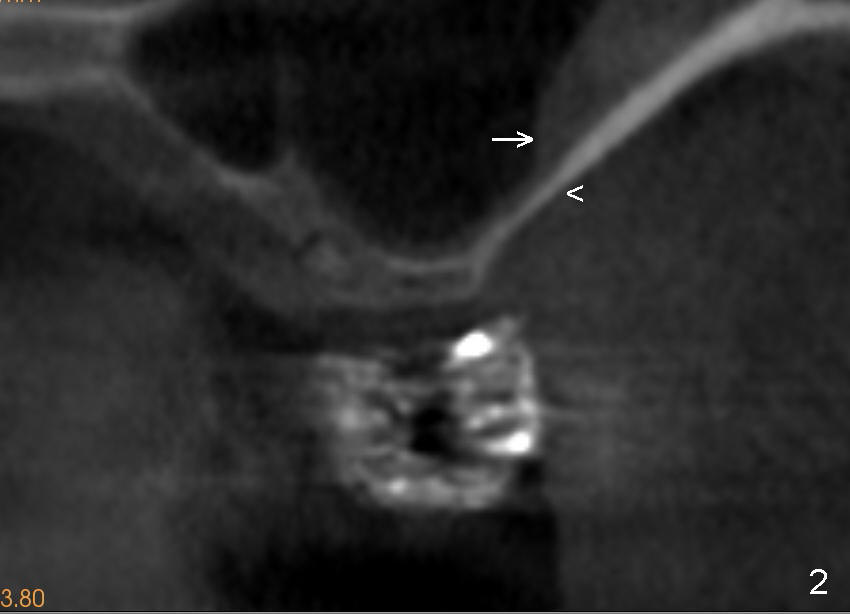

Fig.2 is a CBCT coronal section at the site of #14, as indicated by the dashed line in Fig.1. The arrowhead (<) denotes the anterior bony wall of the maxillary sinus, whereas the arrow (->) the sinus membrane.

These two structure will be lift from the lateral window (arrows in Fig.3) and kept in place with bone graft (red circles in Fig.4).